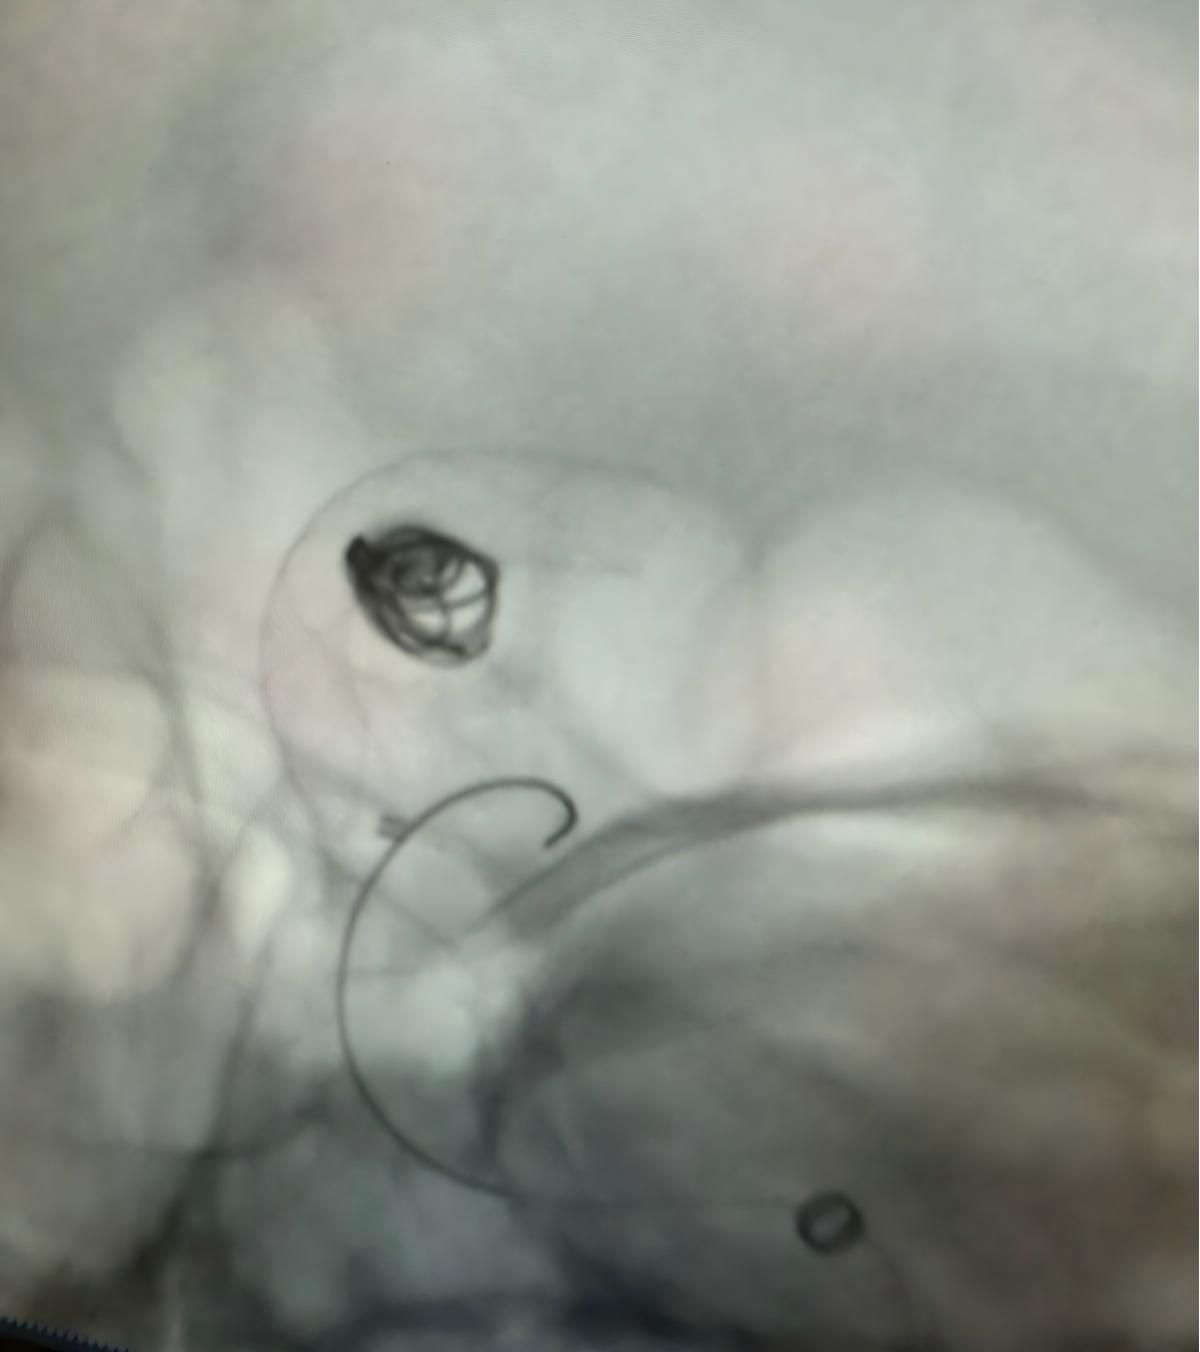

Nos complace compartir un procedimiento exitoso reciente en Clínica Alma Mater, Medellín, realizado por el Dr. Jorge Mutis.

El tratamiento utilizó el Nuva®Desvedor de flujo (TJED-D 5.0-14), Perdenser®Bobina 3D, y el paso de tierra®Microcatéter (TJMC18 Plus) para un aneurisma de arteria comunicante posterior.

Dr. Mutis destacó la excelente visibilidad del dispositivo y señaló que la recuperación fue suave. Expresó su gran satisfacción por el resultado final.